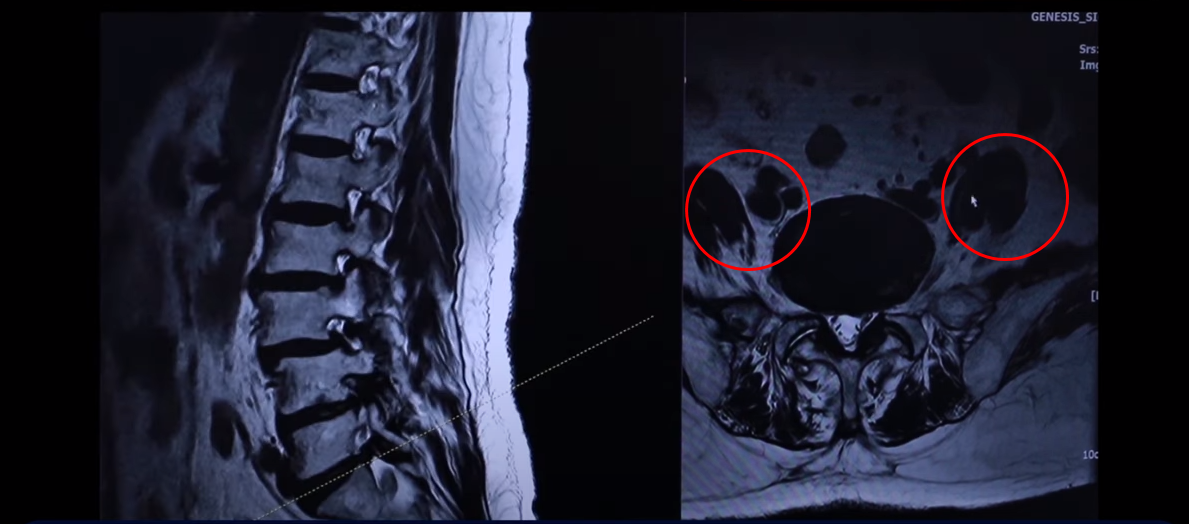

이분 76세 여자 환자분 MRI를 보겠습니다. 이분 MRI를 보시면 보시다시피 허리 여러 마디가 퇴행돼 있고 전방전위가 있습니다. 뼈가 밀려나가 있죠.

그리고 이렇게 뼈가 밀려나간 전방전위증을 가지신 분들은 허리가 오랫동안 아프신 분들이 많습니다. 이분도 한 5년 정도 허리가 아프셨고 그때그때 신경 주사 맞으면서 버티고 사셨는데 신경주사라는 건 맞다 보면 점점 효과가 떨어집니다. 그리고 결국은 다리 증상들이 심하게 생겨서 걷지를 못하게 되시는 거죠. 걷는 거리도 점점 짧아지고 다리는 왜 저리게 되냐면 이분의 이렇게 전방전위증이 있는 마디를 보면 척추관이 좀 좁아져 있지만 아주 많이 좁지 않습니다.

그런데 특히 이 아랫마디 가보면 여기가 많이 좁아져 있습니다. 특히 뭐가 문제냐면 이 척추관보다는 여기 추간공을 보면 이렇게 좁아져 있습니다. 다른 데하고 굉장히 크게 차이가 많이 나죠.

이제 이렇게 환자들이 이런 걸 보시면 아예 까맣게 변해 있다. 신경이 많이 눌리니까 이게 왼쪽 다리로 가는 신경입니다. 그 다음에 오른쪽 다리로 가는 신경을 보면 신경이 여기 지금 까맣게 보입니다. 이 지방이 다 없어져버린 겁니다. 신경 공간이 좁아져 있죠.

그 다음에 이거는 디스크고 이 뒤에 있는 건 황색인대입니다. 이것들이 지금 두꺼워져 있기 때문에 여기 공간이 좁아지는 겁니다. 그래서 이제 오른쪽 다리, 왼쪽 다리가 다 신경이 눌리고 아파서 못 걷는 분입니다.

그러면 이런 분들은 뭐라고 얘기를 듣냐면 수술을 하는데 여러 마디가 안 좋다 보니, 가령 이 마디는 전방 전위가 있고 이 마디는 심하게 양쪽 다리로 가는 양쪽 신경 구멍들이 좁아져 있는 거죠. 그러면 여러 마디 수술을 해야 되는데 또 전방전위도 있기 때문에 나사를 박는 수술을 해야 된다고 듣는 경우가 많습니다.